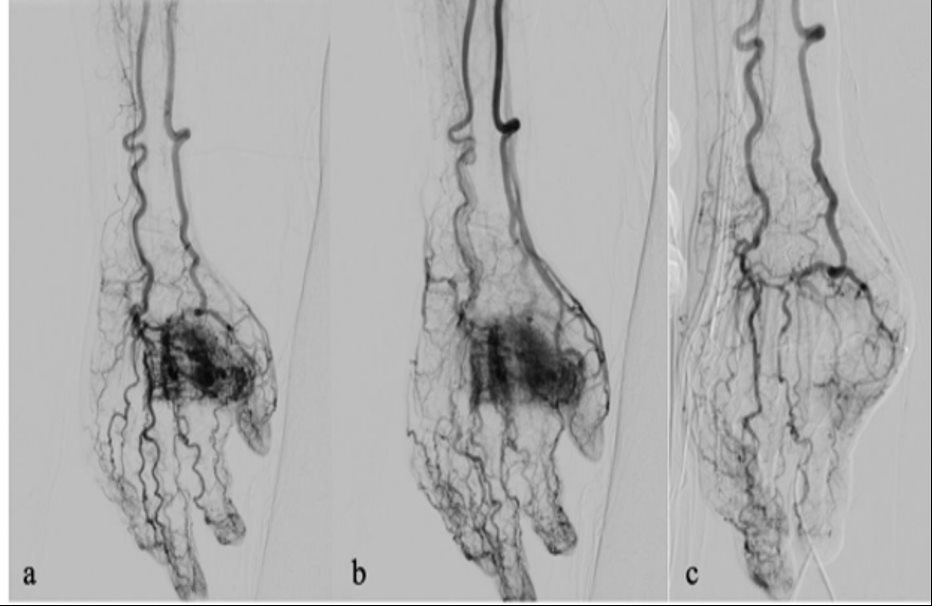

4. Can thiệp dị dạng mạch máu bằng phương pháp tiêm cồn (BV Nhân dân Gia Định)

Trên thế giới, dị dạng mạch máu chiếm tỷ lệ 1% dân số. Trước đây, người bệnh bị dị dạng mạch máu, có rất ít sự lựa chọn để điều trị, người bệnh thường đi đến nhiều bệnh viện để tìm các phương pháp điều trị thích hợp.

Với những trường hợp dị dạng mạch máu nhỏ như bướu máu nhỏ khu trú dưới da có thể mổ để lấy ra dễ dàng, nhưng thường các dị dạng mách máu rất phức tạp, ảnh hưởng đến xương, cơ và biến dạng về mạch. Việc phẫu thuật được xem là phương pháp lựa chọn duy nhất để can thiệp.

Từ năm 2016, với sự giúp đỡ của các chuyên gia nước ngoài, Bệnh viện Nhân dân Gia Định đã chính thức áp dụng kỹ thuật điều trị dị dạng mạch máu bằng phương pháp tiêm cồn, giúp điều trị thành công nhiều trường hợp. Tỷ lệ thành công đạt 90% đối với dị dạng chung, tỷ lệ biến chứng thấp (<2%). Ngoài ra với kỹ thuật điều trị dị dạng mạch máu bằng phương pháp tiêm cồn có giá thành thấp.